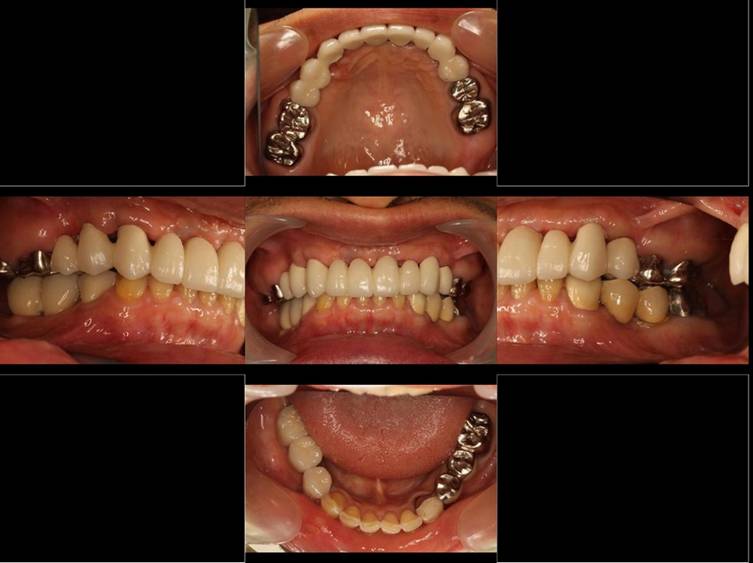

歯周病で抜歯せざるを得ず、インプラントを希望されたケース(使用インプラントはスプライン)

術前。すべての歯が歯周病の末期状態でブリッジ全体がうごいて噛めないとの訴え。右上の犬歯が腫れていました

固定式のブリッジが入っていましたが歯周病で動いています

下顎前歯部には歯石の沈着がみられます